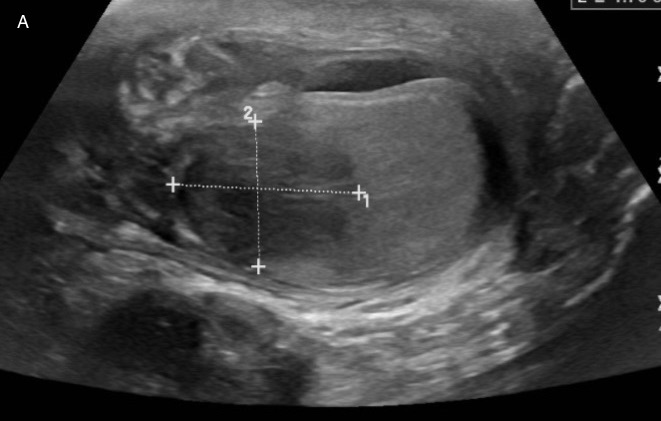

Case Presentation: A 44-year old Chin-Mizo speaking male with a history of stage IV non-small cell lung cancer presented to the Emergency Department with acute-onset hematuria and painless right testicular swelling. Physical examination revealed an enlarged right hemi-scrotal mass and painful nodular skin lesion on right posterior calf. A transverse ultrasound image of the scrotum showed mass-like hypoechoic lesion in the right testicle measuring approximately 2.3 x 1.8 cm (Panel A) and a corresponding color Doppler image showed an asymmetric hypervascularity of the right testicle and epididymis. A PET CT scan confirmed a lobulated and hypermetabolic mass in the right scrotum measuring 4.7 x 3.4 cm. MRI of right lower leg showed a cystic-like lesion in the periphery of the lateral gastrocnemius muscle. The patient underwent right inguinal orchiectomy along with biopsy of the leg lesion. Histopathology of right testis H&E stain revealed necrotizing acute and chronic diffuse granulomatous inflammation with giant cells surrounded by fungi. A GMS stain showed broad based budding yeast (arrows, Panel B). Tissue culture grew Blastomyces dermatitidis/gilchristii. Given these findings, the patient was diagnosed with disseminated Blastomycosis. Patient was started on treatment with Amphotericin B and transitioned to Itraconazole upon discharge with recommendation to follow with Infectious Disease in outpatient clinic.

Discussion: Blastomycosis is a systemic pyogranulomatous infection that can disseminate to involve any organ in the body and mimic other granulomatous infections such as tuberculosis. Most common involved extrapulmonary sites of infection include skin, bones, and genitourinary system with commonly affected sites are prostate and epididymis. The infection occurs with increased frequency in the Great Lakes, Southeast and along the Ohio and Mississippi river valleys. Other risk factors include immunosuppression and outdoor occupation. Blastomycosis is acquired by inhalation of the spores and disseminates from a primary pulmonary infection to other organs by lymphohematogenous spread. The patient’s bronchoscopic culture was negative for infection. Given the mass-like appearance on scrotal US, a malignancy vs epididymo-orchitis was initially considered. The increased flow within the testicular lesion and epididymis is suggestive of an inflammatory cause and the mass in the testicle was well defined as opposed to the typical ill-defined appearance of orchitis.